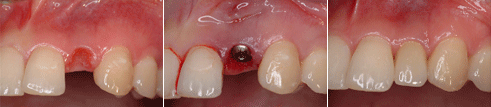

상한 앞니를 발거하고 즉시 임플란트를 식립하여 회복한 증례 임플란트 식립을 위한 골 증대술

상한 앞니를 발거하고 즉시 임플란트를 식립하여 회복한 증례 - 상악동 거상술을 통한 골 이식술